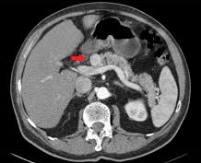

- Инструментальная визуализация. Для выявления объемного образования используют все доступные способы: ультразвуковую диагностику, рентгенографию, компьютерную и магнитно-резонансную томографию. При ПЭКоме органов пищеварения применяют эндоскопическую диагностику: ЭФГДС, ЭРХПГ, колоноскопию.